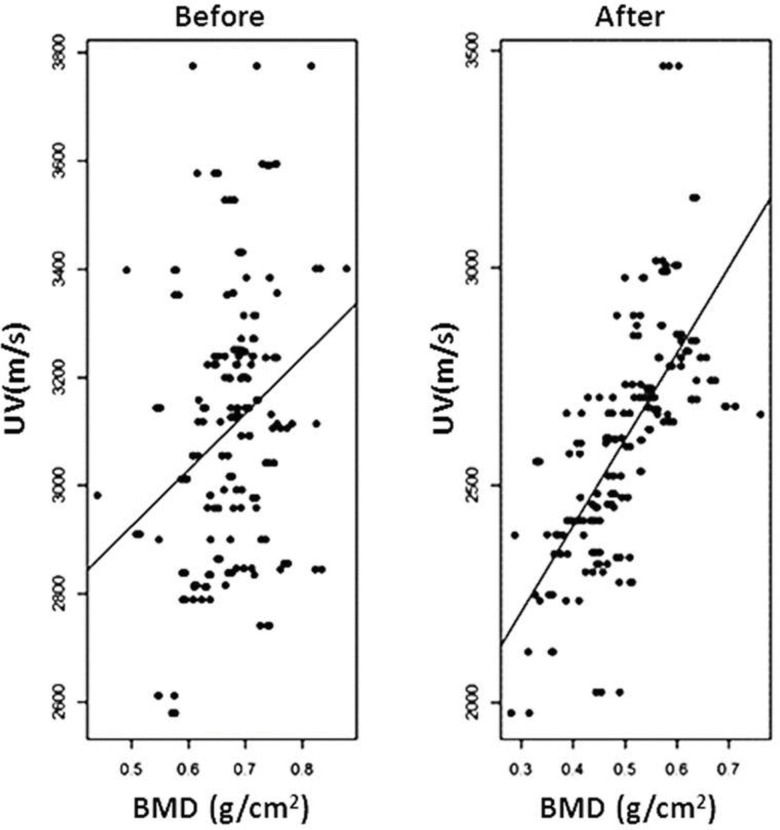

The correlation between UV and BMD progressively increased with the post-demineralization period (G6: r=0.38308, p=0.0002; G12: r=0.64451, p<0.0001; G24: r=0.88733, p<0.0001; G36: r=0.89270, p<0.0001), with a relatively high overall correlation of r=0.75956 (p<0.0001) (Figure 7).

UV and BMD figures were then transformed into percent values of baseline, taking the pre-demineralization values as the baseline. The differences and averages of the obtained values were then applied to a Bland-Altman graph to evaluate the agreement between the two methods. The Bland-Altman graph allows for visualization of how much each difference deviates from zero (bias), the dispersion of the differences around the average (error) and the tendency of the distribution. A perfect agreement occurs when the mean (bias) is zero and the dispersion between the upper (ULA) and lower (LLA) limits of agreement is very small or as close as possible to the mean line; data above ULA and below LLA are not in agreement. In the present case, a moderate agreement was observed because the mean was well above the zero line [9.44] and the average dots were dispersed around the mean line, although concentrated between the ULA and LLA lines. A single case was above ULA, while four cases were below LLA (Figure 8). The dot distribution also showed that lower percent differences between UV and BMD corresponded to averages closer to 100 and that this tendency of the comparison likely indicates that the agreement between the two methods is easier to detect in normal untouched bones.